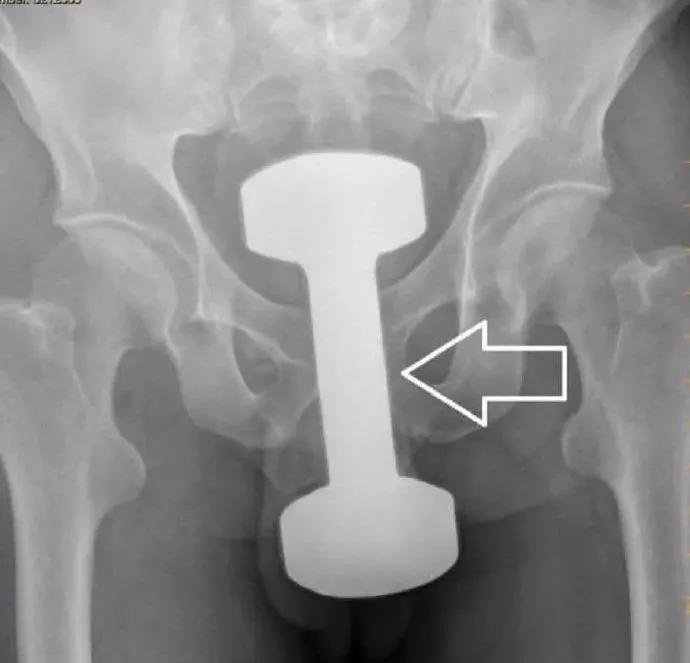

西南医科大学附属中医医院肛肠科主任李五生教授说:直肠异物是直肠里出现除了粪便以外的其他东西,比如灯泡、按摩棒、玻璃药瓶、陀螺、蜡烛、圆柱形金属瓶等等,甚至常见的蔬菜和长条状的物体,比如黄瓜、火腿肠、茄子、苦瓜、黄鳝、泥鳅……

正常的肛门括约肌一般处于闭合状态,借用外力往肛门里塞入异物时比较容易,异物塞入后括约肌回缩,像给肛门口“上锁”一样,取出时就变得困难。异物可能会引起肠梗阻、肠道水肿、感染,甚至损伤肠管导致肠穿孔,危及生命!